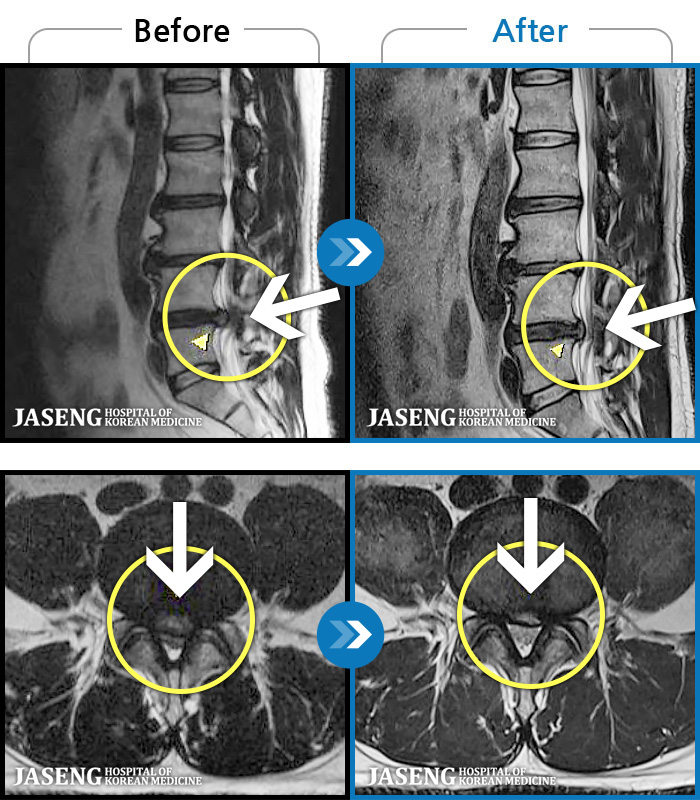

Before

After

허리 통증과 양측 둔부부터 허벅지, 발목 부위 저리는 증상으로 내원하셨습니다.

2025.05.09 ~ 2025.12.18